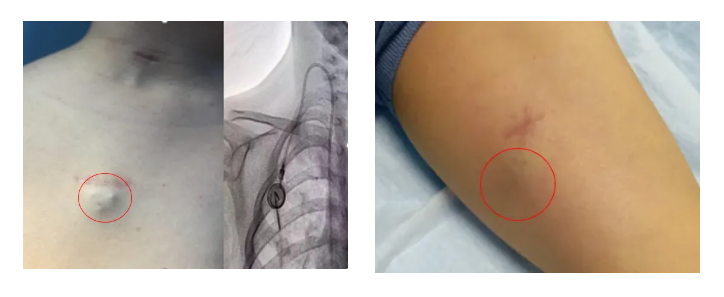

輸液港,即完全植入式輸液港(PORT),是一種可完全植入皮下并長期留存體內(nèi)的輸液裝置,主要由注射座(又稱港體)和硅膠導管兩部分組成。注射座被埋植于胸部皮下,導管則連接到上腔靜脈,形成一個閉合的靜脈輸液系統(tǒng)。其常見類型有手臂輸液港與胸壁輸液港。